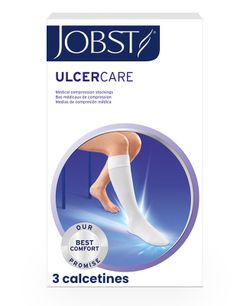

Jobst Relief 1 Long Stockings Long Stockings with Waist Support AG-T Medium Compression (Class 2 20-30 mmHg) Post-Operative 1 Unit

Brand: Jobst

Reference: 045784

Description

Jobst Relief Medium Compression Stockings Class 2 20-30 mmHg AG-T 1 Unit. A quality solution for the postoperative period. Jobst ® Relief ® provides adequate therapeutic compression with an indisputable quality/price ratio, especially important in those short-term postoperative treatments.